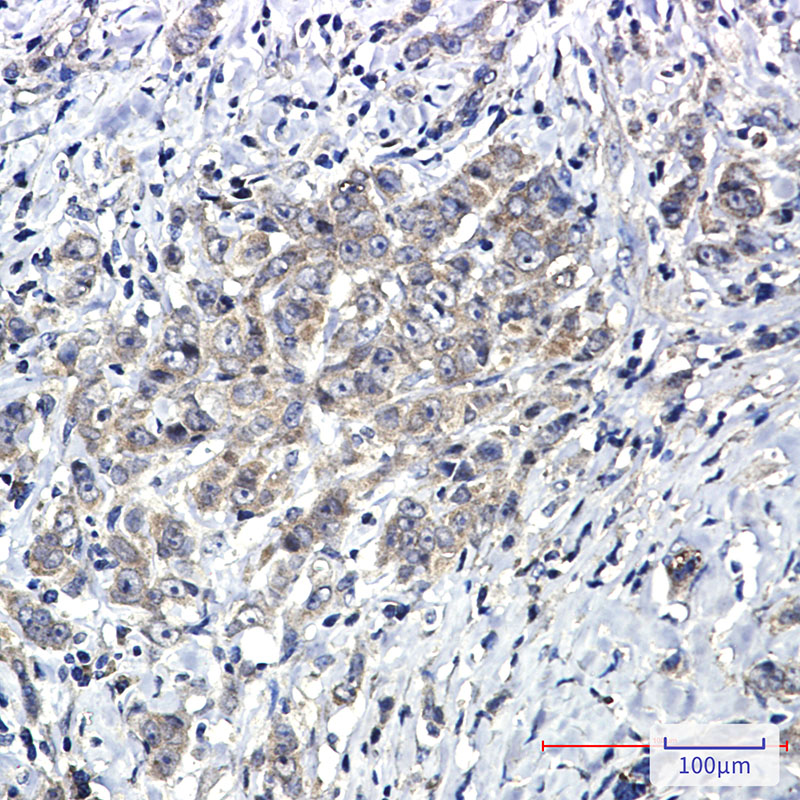

Immunohistochemistry analysis of paraffin-embedded Human breast cancer using SHP2 antibody.High-pressure and temperature Sodium Citrate pH 6.0 was used for antigen retrieval.